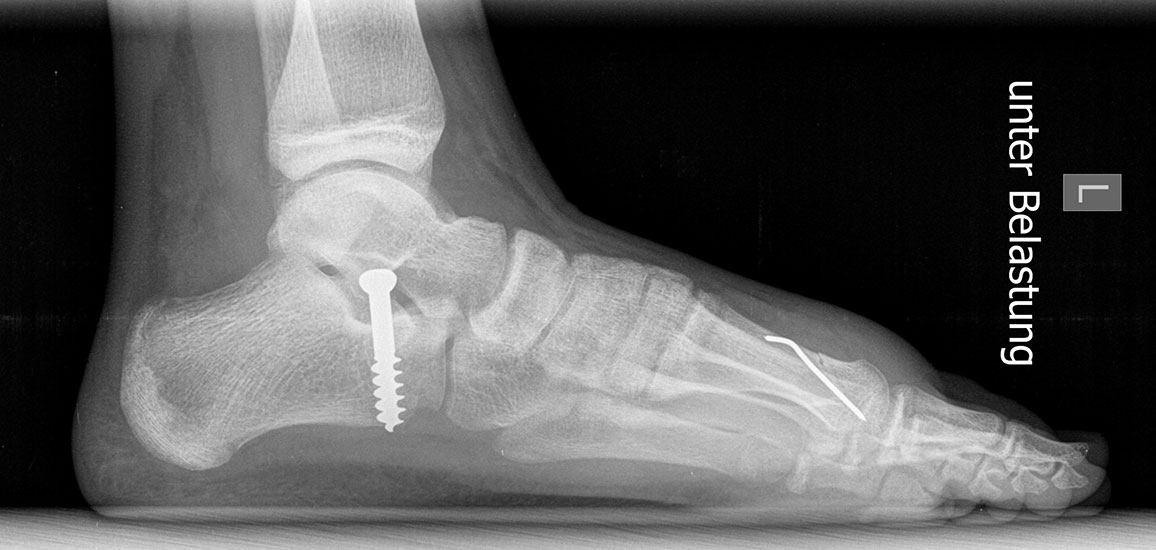

Röntgen

Standard ist die belastete Röntgenaufnahme des Fußes dorso-plantar und seitlich. Günstig ist eine Röhrenkippung von 10°-20°, um die Gelenke der Lisfranc-Linie einsehen zu können.

Ergänzend kann eine Schrägaufnahme hilfreich sein. Bei Metatarsalgien oder Pathologien der Sesambeine liefert die Sprinteraufnahme zusätzliche Informationen. Bei einer Pes planovalgus Fehlstellung wird ergänzend ein Saltzman view durchgeführt.

• Elevation/ Plantarisierung I. Strahl

• Pes metatarsus adductus